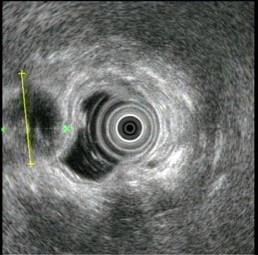

问题 患者,38岁,进食后常有上腹不适多年,1个月前发作一次右上腹剧痛,无腹膜炎体征,超声内镜如图中,胆囊病变可能的诊断是 ( )

选项 A、胆囊多发息肉 B、胆囊多发结石 C、胆囊腺肌病 D、胆囊癌 E、胆囊积脓

答案 B